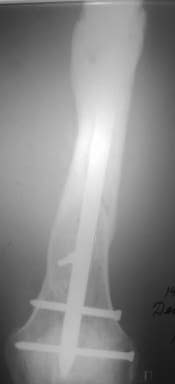

Александр Николаевич, к сожалению больной не является на контрольные осмотры. Я последний раз видел больного, когда прошло 7 месяцев после операции БОС. У него все хорошо. Каких либо жалоб и ограничений в нагрузке нет. Высылаю снимки до операции и последние снимки.

У нас, наверно, была бы сделана чрескожная остеотомия малоберцовой кости, формирование и рассверливание канала большеберцовой, закрытая остеоклазия, и закрытое же штифтование. За счет устранения варуса дефицит длины уменьшится. Можно и подтянуть дистрактором одномоментно.

Костная пластика при закрытом остеосинтезе не нужна.